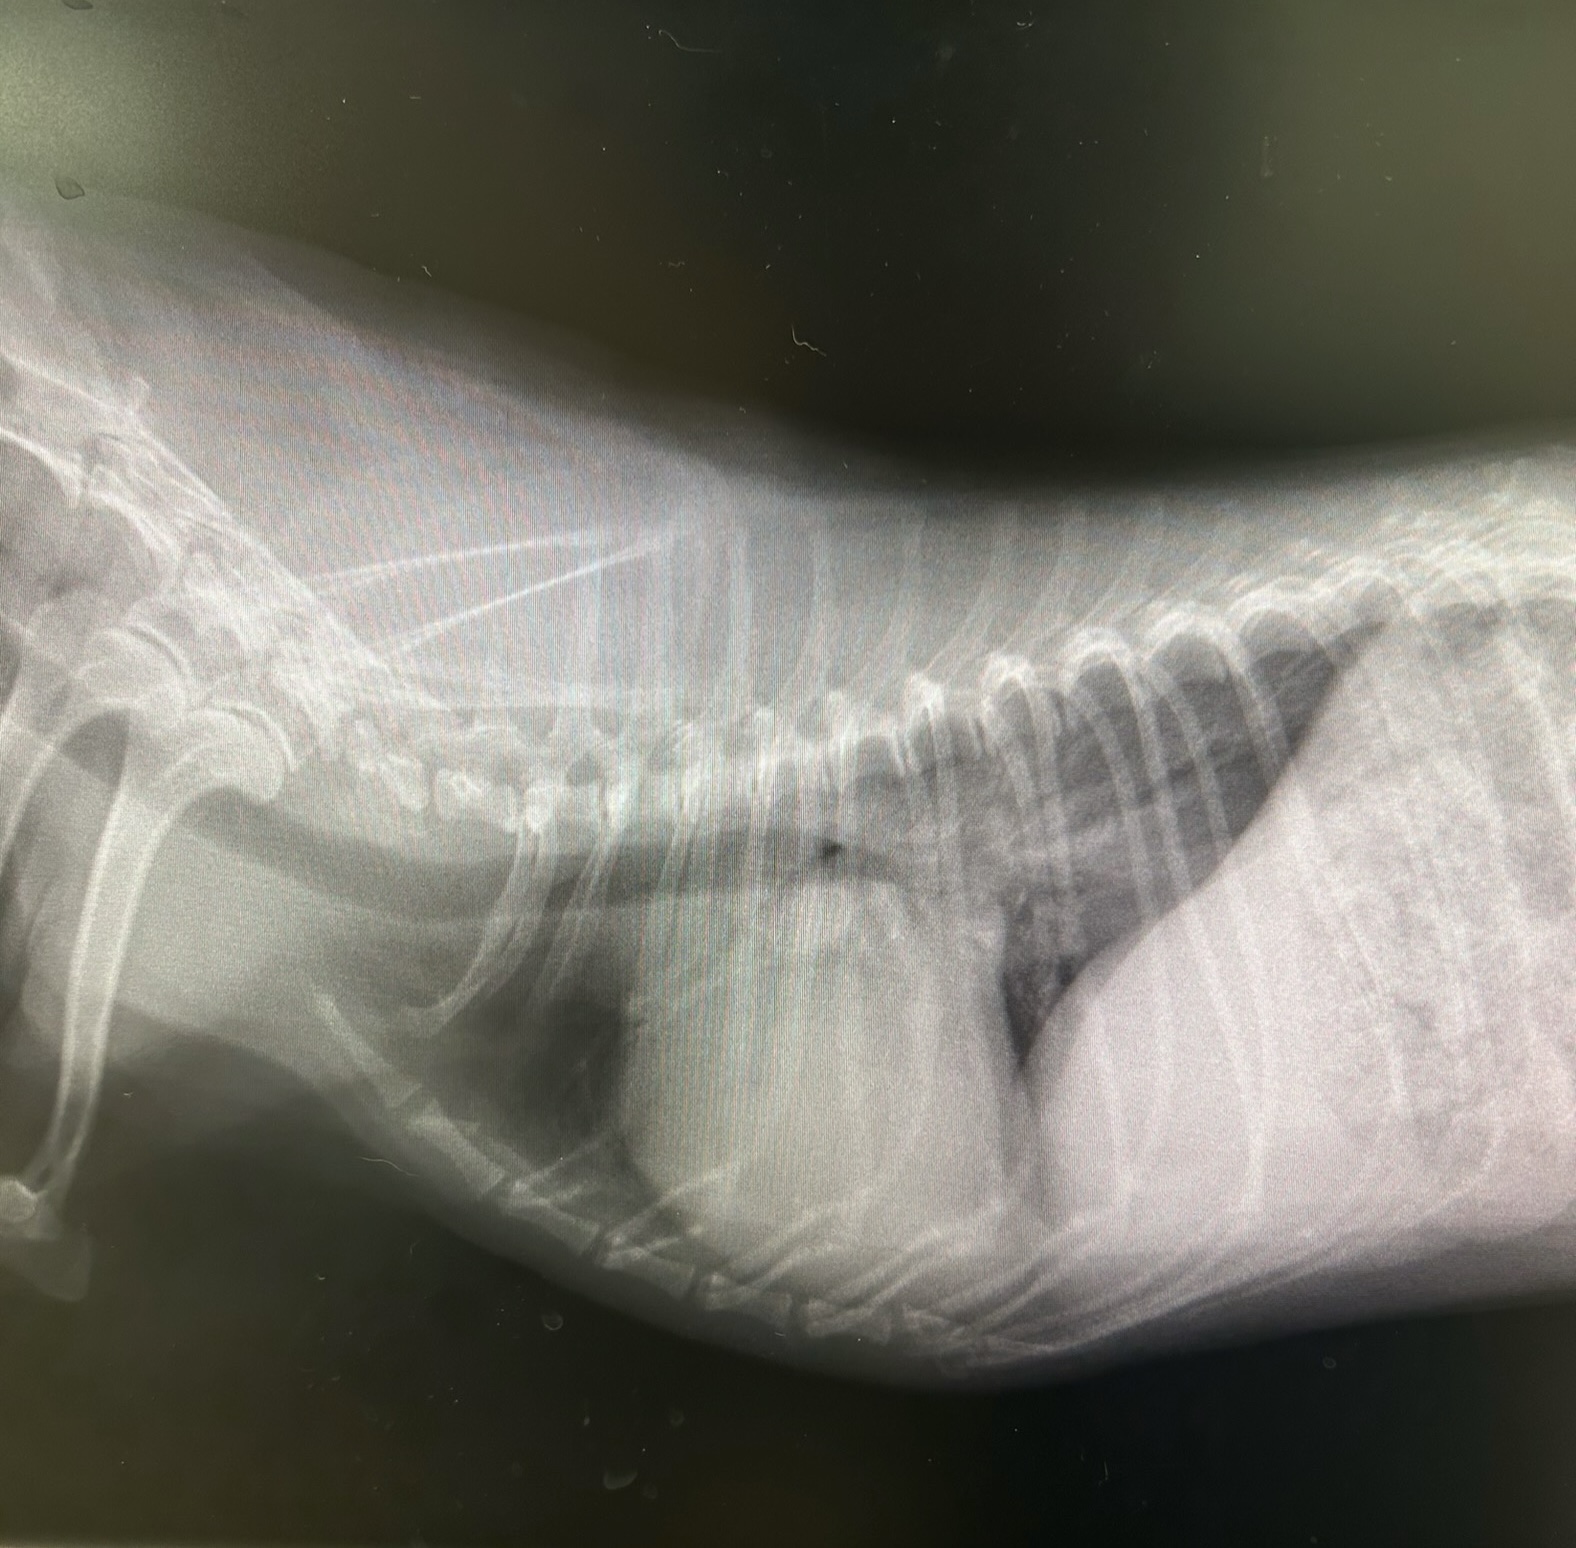

HOT ! イヌの僧帽弁閉鎖不全症 イヌの僧帽弁閉鎖不全症: 診断・管理の理論と実際 | 竹村直行

イヌの僧帽弁閉鎖不全症 イヌの僧帽弁閉鎖不全症: 診断・管理の理論と実際 | 竹村直行の詳細情報

イヌの僧帽弁閉鎖不全症: 診断・管理の理論と実際 | 竹村直行。犬の僧帽弁閉鎖不全症について | 柴田動物病院 (アニコム。僧帽弁閉鎖不全症 |。僧帽弁閉鎖不全症】犬の僧帽弁閉鎖不全症とは?症状や治療法を。イヌの僧帽弁閉鎖不全症若干シミがありますが読むには影響ございません。犬の僧帽弁閉鎖不全症の症状や原因、治療法について獣医師が解説。

• イヌの僧帽弁閉鎖不全症: 診断・管理の理論と実際 | 竹村直行

• 犬の僧帽弁閉鎖不全症の症状や原因、治療法について獣医師が解説